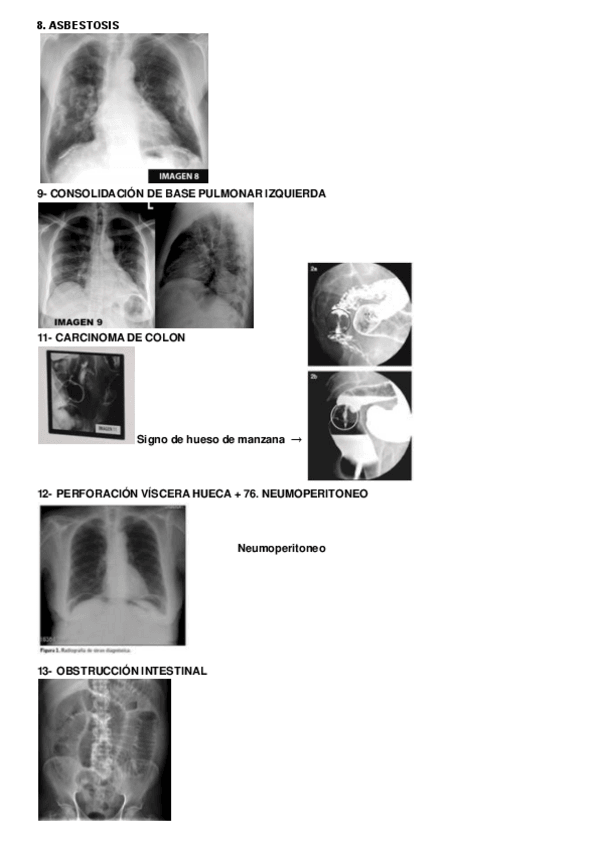

Tema-7-anatomia-radiologica-del-torax.pdf

Tema-7.-Anatomia-radiologica-torax.pdf